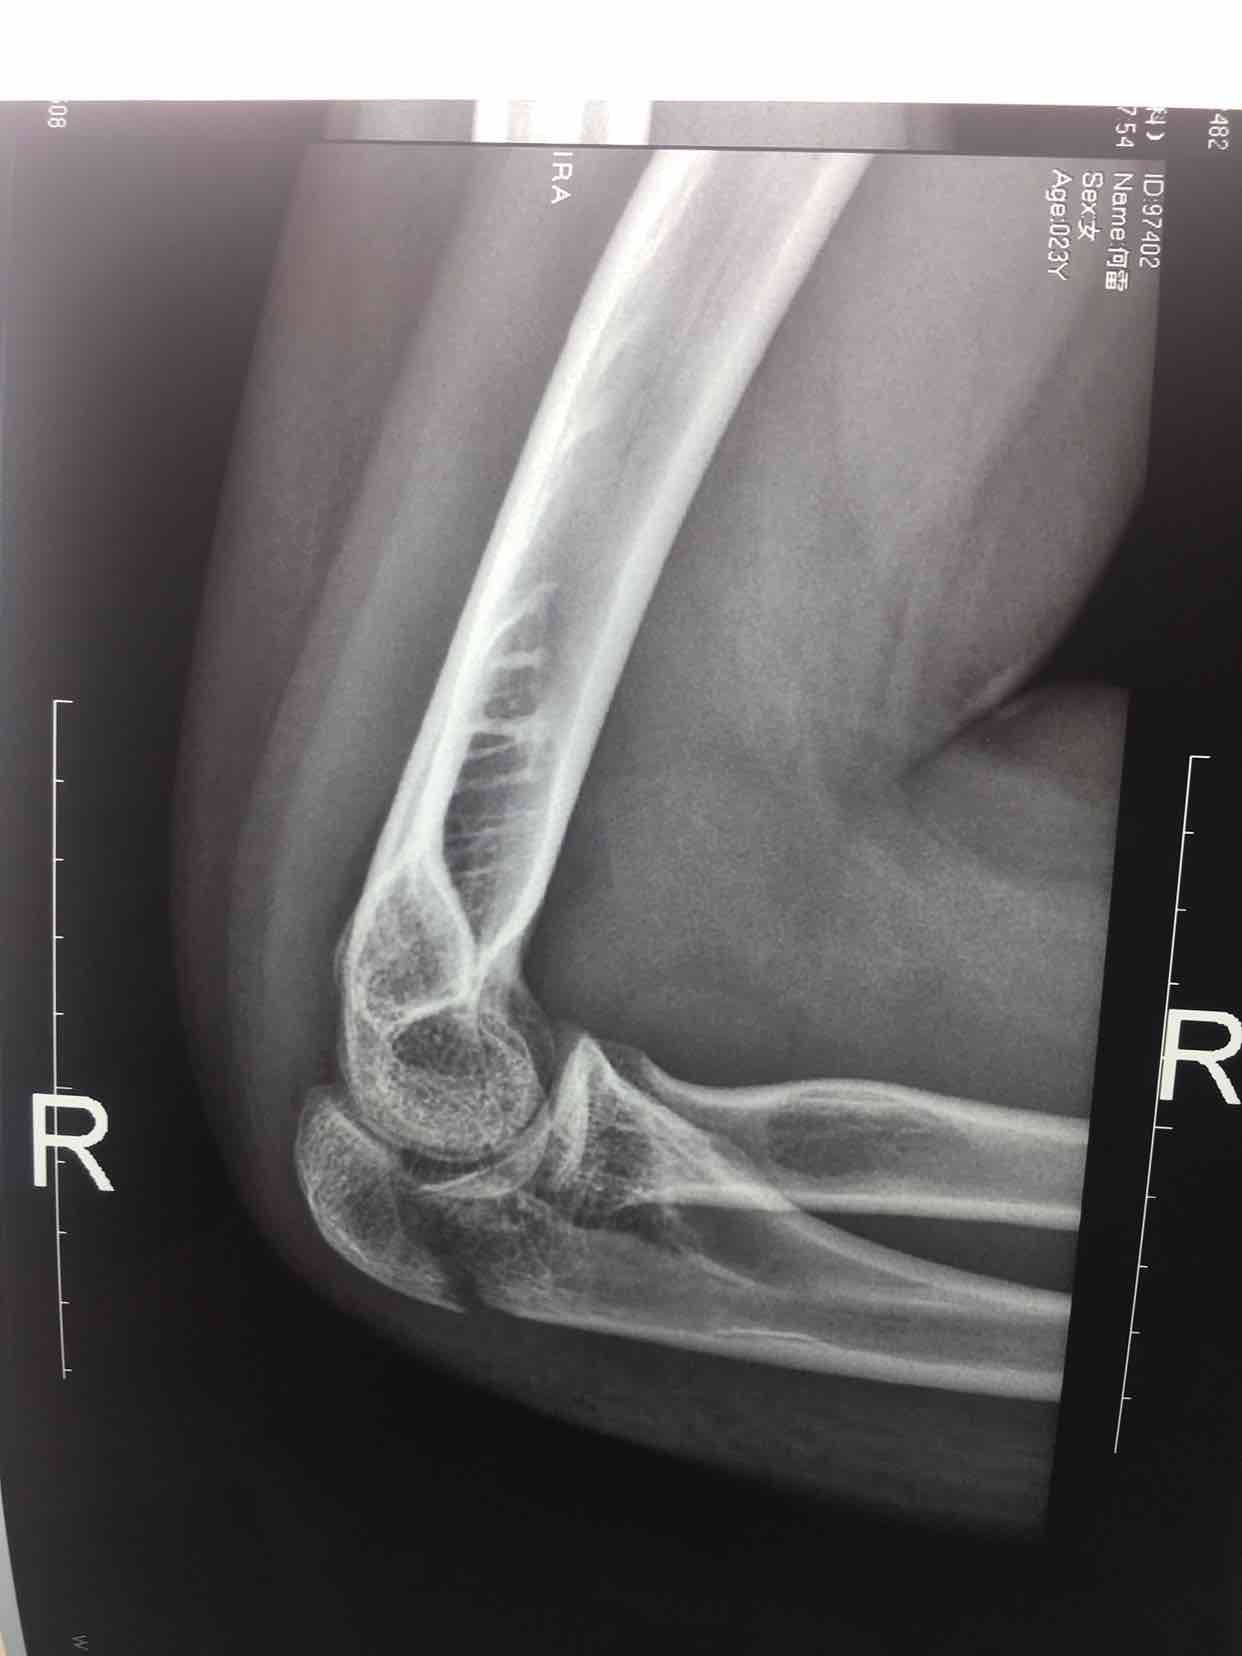

尺骨鹰嘴骨折(切复内固定术)

骨折 鹰嘴骨折

摔伤后右肘部肿痛,活动受限1小时入院。既往身体健康,无特殊不良嗜好。

生命体征平稳,心肺复未见异常。右肘部肿胀明显,局部皮色皮温正常,压痛明显,可及骨檫音,末梢血运感觉正常。

诊断右尺骨鹰嘴骨折在臂丛麻醉下行切复内固定术,术后抗炎,消肿等处理。